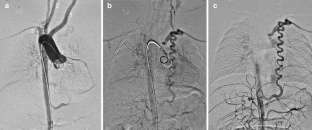

An isolated left subclavian artery is a rare anomaly. We report a 9-month-old boy with an isolated left subclavian artery associated with tetralogy of Fallot and the right aortic arch. MRI and angiography show that the blood supply through the left subclavian artery was maintained by a large tortuous collateral artery from the abdominal aorta. This type of collateral artery structure is unique.

Fig. 1